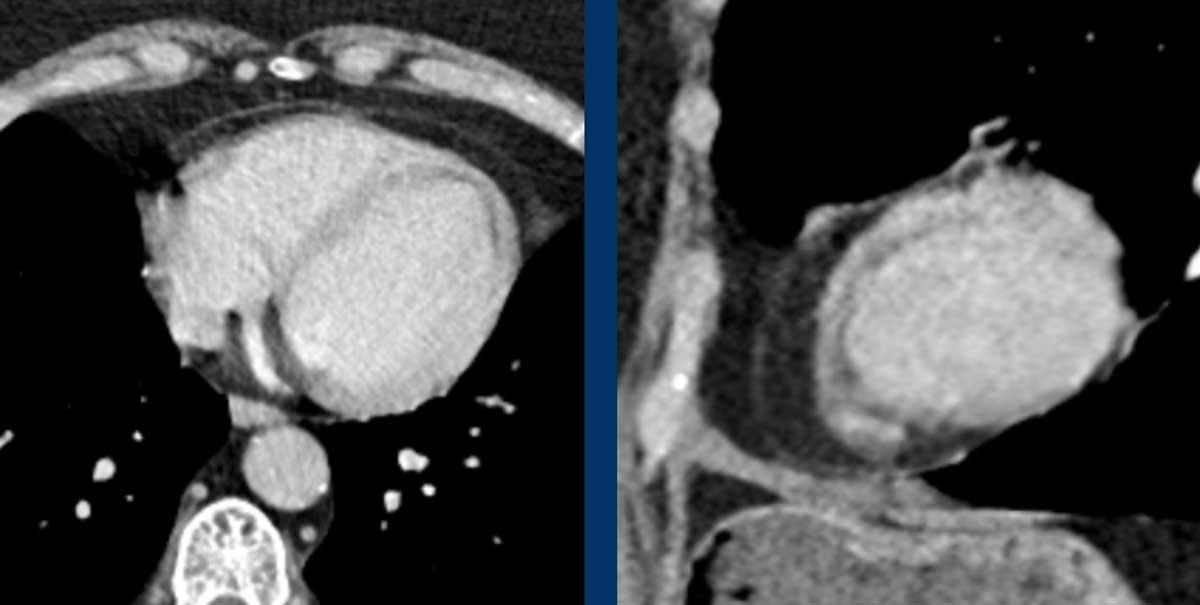

Hình ảnh

Giãn phình nặng xoang động mạch chủ và động mạch chủ đoạn lên.

Khi phát hiện giãn động mạch chủ đoạn gần, cần tiến hành đánh giá kỹ lưỡng hơn các bất thường có thể liên quan như hẹp van động mạch chủ hoặc van động mạch chủ hai lá.